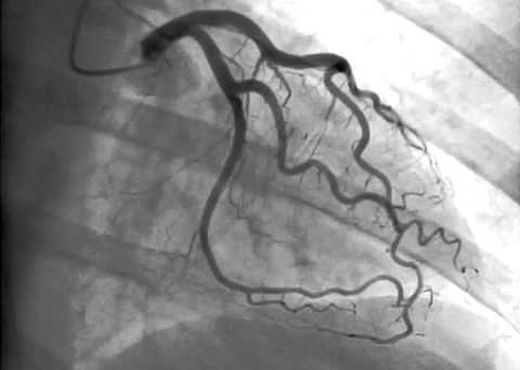

El estudio incluyó 15888 pacientes sin historia conocida de enfermedad coronaria que recibieron una coronariografía electiva entre 1996 y el 2010 en el Duke University Medical Center.

En el presente análisis, los pacientes con angina típica mostraron la tasa más alta de enfermedad coronaria. El 74.3% de los paciente con síntomas típicos pero con prueba de esfuerzo negativa tuvieron enfermedad coronaria significativa en la coronariografía.

En aquellos con síntomas típicos pero que no se realizaron una prueba de esfuerzo y fueron directo a coronariografía se observó una tasa de enfermedad coronaria de casi el 70%.

La tasa más baja de enfermedad coronaria obstructiva (24.6%) se observó en aquellos con síntomas atípicos o sin síntomas y prueba de esfuerzo positiva.